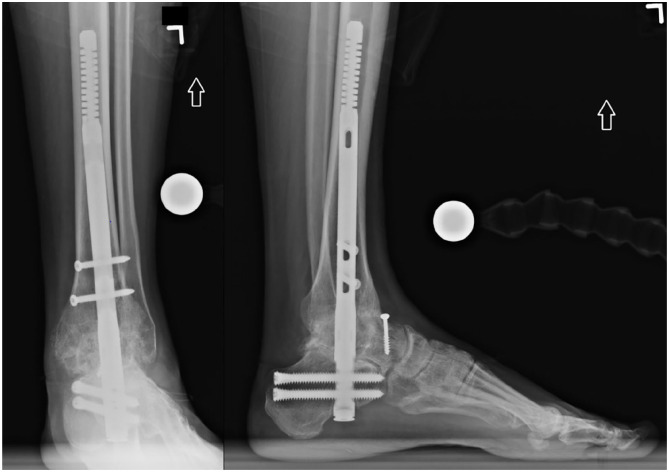

Methods: Inclusion criteria consisted of patients who had undergone a tibiocalcaneal or TTC arthrodesis using the Phantom Hindfoot TTC Nail System with at least 6 months of follow-up. Radiographic analysis evaluated for successful union and flexibility of the flex coil. Patients were monitored for postoperative complications and additional secondary procedures.

Results: Twenty-one patients were included and had an average follow-up of 9.4 ±4.7 months (range, 4.3-19 months). No intraoperative complications were reported. Seven patients experienced at least 1 adverse event, which included device migration, asymptomatic nonunion, symptomatic nonunion, bone stress reaction, device prominence, and screw breakage. There were no events of perioperative fractures or device breakage. Two patients required secondary surgical interventions. The 5 remaining patients were managed conservatively. An average nail coil flexion angle of 2.6 ± 3.1 degrees and 0.8 ± 1.59 degrees was found on lateral and anteroposterior radiographs, respectively. The overall union rate at a mean follow-up of 9.4 months was 90.4% (95% CI 69.6%, 98.8%).

Conclusion: TTC arthrodesis via the AC nail demonstrated similar union rates and outcomes at short-term follow-up compared with rates generally reported in the literature for other IM nail constructs. The AC nail was able to function as designed and allow for motion at the proximal bone-implant interface.